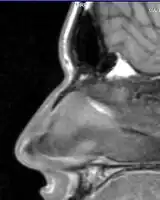

Nasal bone fracture

Bilateral nasal fracture as seen on CT scan